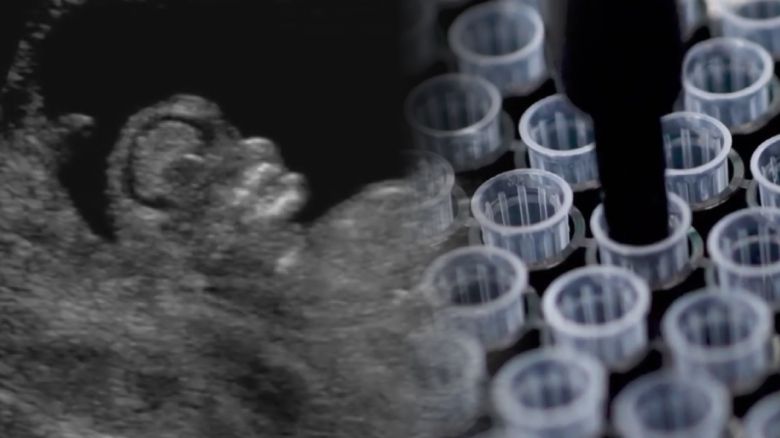

CNN은 컬럼비아대 난임센터가 AI 기술을 도입한 이른바 STAR(Sperm Tracking and Recovery) 정자추적 시스템으로 난임 부부 임신에 성공했다고 보도했습니다.

정액 샘플을 특수 설계된 칩에 올려놓은 뒤 고속 카메라와 고출력 이미징 기술로 샘플을 스캔해 정자를 찾아내는 방식입니다.

정자 세포로 인식하도록 학습된 AI가 800만 개 이상의 이미지를 분석해 한 마리 한 마리씩 정자를 찾아낸 겁니다.